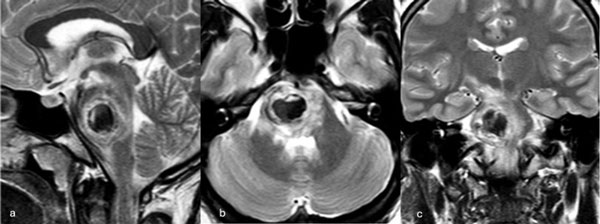

Caso 2: cavernoma pontino

Una paciente femenina de 28 años, sin antecedentes de sangrado previo, debutó con cefalea, náuseas y vómitos, asociado a diplopía secundaria a una parálisis del VI par derecho. La RM de encéfalo evidenció una malformación cavernomatosa centrada en puente y el pedúnculo cerebeloso medio derecho (Figura 3). Un mes después del sangrado, se realizó una exéresis de la lesión mediante un abordaje retrosigmoideo ampliado a través del pedúnculo cerebeloso medio (Figura 4), logrando una exéresis completa (Figura 5). Tras el procedimiento, la paciente evolucionó con hemihipoestesia del hemicuerpo izquierdo, sin otros síntomas agregados.

Figura 3. RM preoperatoria de encéfalo. Se evidencia una lesión única intraaxial centrada en puente y pedúnculo cerebeloso derecho, sugerente de un cavernoma roto. A, B y C) Imágenes ponderadas en T2 en cortes sagital, axial y coronal, respectivamente, donde se observa un importante hiperintensidad perilesional, sugerente de edema.

Figura 4. Imágenes intraoperatorias bajo microscopía. Abordaje retrosigmoideo ampliado a derecha, con ruta de ingreso transpedúnculo cerebeloso medio. A yB) Corticotomía en pedúnculo cerebeloso medio. C) Identificación y resección en bloque de la malformación cavernomatosa. D) Revisión del lecho, sin remanente.

Figura 5. RM postquirúrgica de encéfalo. Se evidencia una exéresis completa con hiperintensidad en T2 en regresión. A, B y C) Imágenes ponderadas en T2 en cortes coronal, axial y sagital, respectivamente.

Caso 3: cavernoma pontino

Un hombre de 37 años, con antecedentes de hipertensión arterial, debutó con ataxia de la marcha, nistagmo y hemihipoestesia facial izquierda y braquiocrural derecha. La RM de encéfalo evidenció una malformación cavernomatosa centrada en la protuberancia y el pedúnculo cerebeloso medio izquierdo (Figura 6). Un mes después del sangrado, el paciente fue sometido a una exéresis de la lesión mediante un abordaje retrosigmoideo ampliado por izquierda a través del pedúnculo cerebeloso medio (Figura 7), logrando una exéresis completa (Figura 8). Después del procedimiento, el paciente evolucionó con persistencia de los síntomas de ingreso, pero sin agregar nuevos déficits.

Figura 6. RM preoperatoria de encéfalo. Se evidencia una lesión única intraaxial localizada en el puente y pedúnculo cerebeloso medio izquierdo, hiperintensa en T1 y con un anillo hipointenso en T2, característica de una malformación cavernomatosa con sangrado reciente. A) Imagen ponderada en T1 en corte sagital. B y C) Imágenes ponderadas en T2 en cortes axial y coronal, respectivamente.

Figura 7. Imágenes intraoperatorias bajo microscopía. Abordaje retrosigmoideo ampliado a izquierda, con ruta de ingreso transpedúnculo cerebeloso medio. A) Apertura de fisura horizontal que divide los lóbulos semilunar superior y semilunar inferior del cerebelo, exponiendo el pedúnculo cerebeloso medio. B) Corticotomía en pedúnculo cerebeloso medio, evidenciando la cápsula del cavernoma. C) Resección en bloque de la malformación cavernomatosa. D) Revisión del lecho, sin remanente.

Figura 8. RM postquirúrgica de encéfalo. Se evidencia una exéresis completa, sin daño del parénquima adyacente. A, B y C) Imágenes ponderadas en T2 en cortes coronal, axial y sagital, respectivamente.